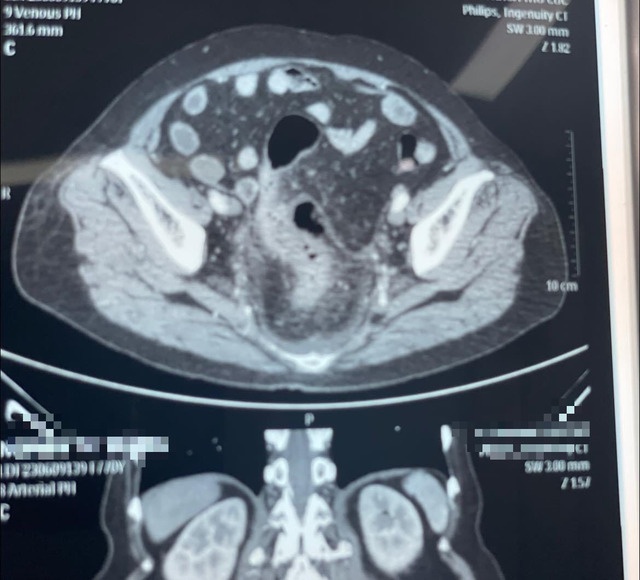

Qua thăm khám và chụp CT phát hiện một ổ áp xe lớn trong ổ bụng do thủng trực tràng, bệnh nhân đã được mổ cắt đại tràng và làm hậu môn nhân tạo với hậu phẫu khá nặng nề vì tình trạng nhiễm trùng, nhiễm độc.

Hình ảnh chụp CT phát hiện một ổ áp xe lớn trong ổ bụng do thủng trực tràng do tự thụt rửa đại tràng tại nhà.